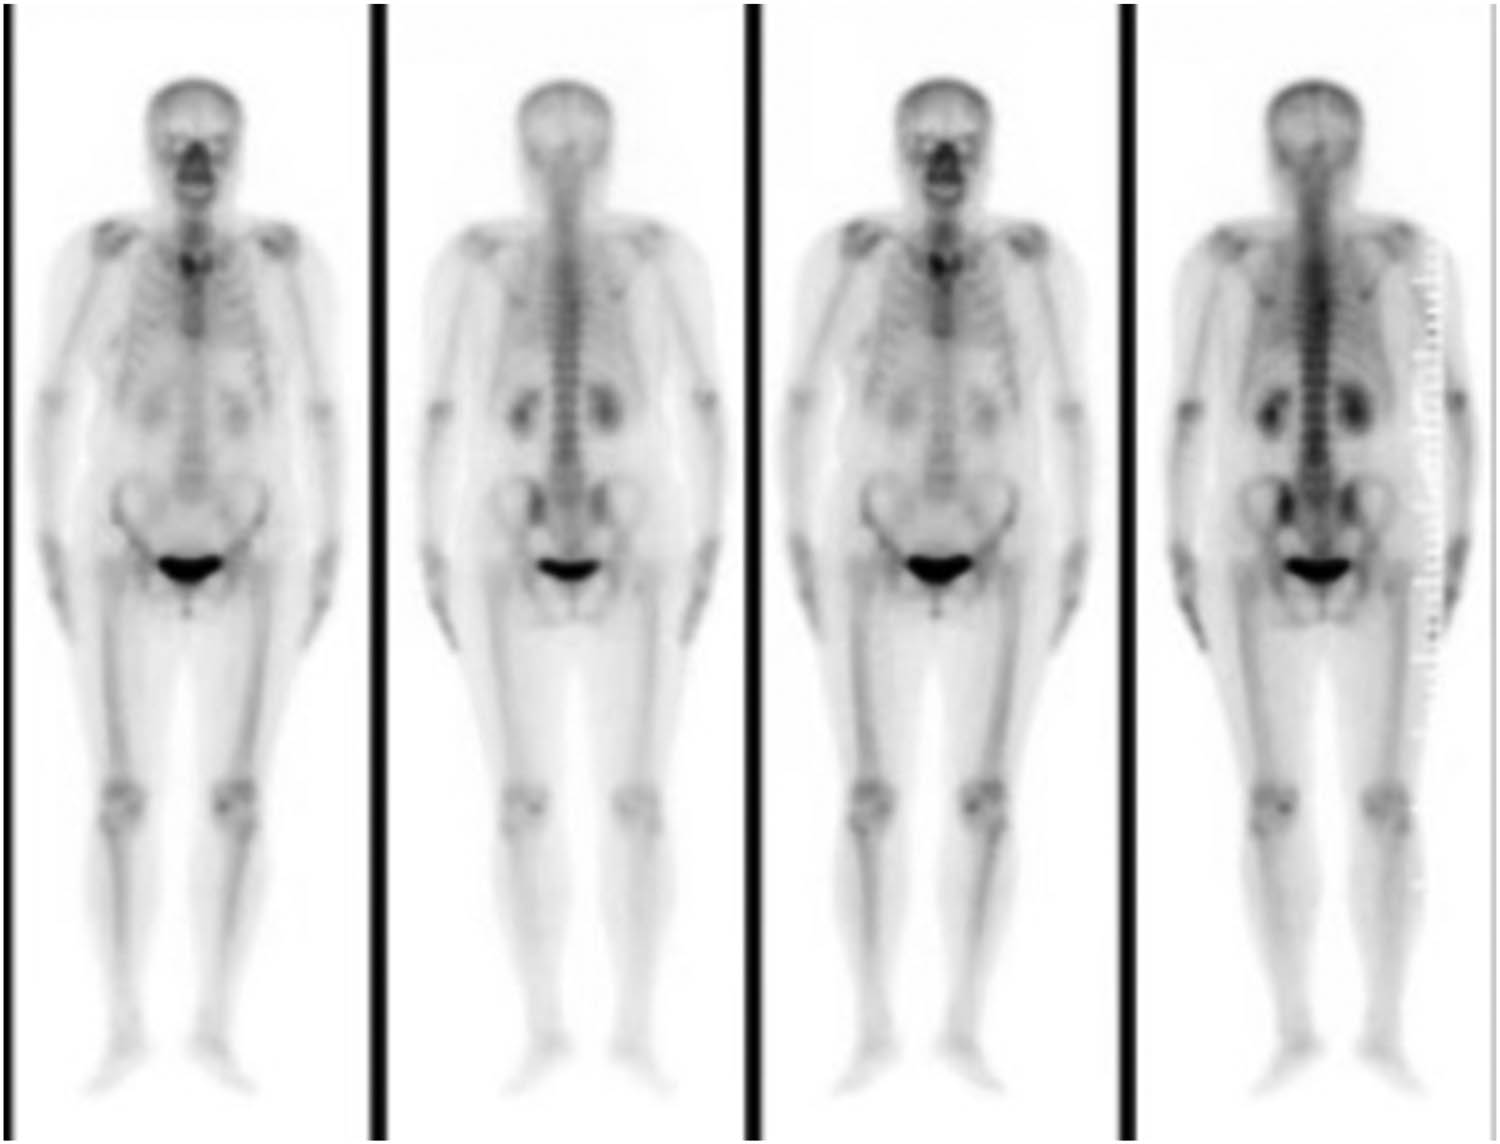

A 56-year-old female, who had lung cancer and undergoing wedge resection of the upper left lung, presented with subacute onset, progressive, right thoracic back pain for several days. Her pain worsened at night and the Visual Analogue Scale (VAS) was 8/10. A neurological exam showed normal motor function, normal sensation, and no abnormal reflexes. The patient had point tenderness over the T7 regions. Magnetic resonance imaging showed that the lesion was located at the right transverse process of T7. The vertebral body was not destroyed and the cervical spinal cord was not compressed (Figure 1). Bone scan showed diffuse increased uptake of the isotope at the level of the right transverse process of T7, without other abnormalities elsewhere in the skeleton (Figure 2).

Bone scan showed diffuse increased uptake of the isotope at the level of the right transverse process of T7.